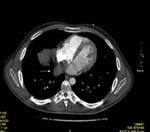

Methods: Twenty-two patients referred to our department with a suspected cardiac mass, previously detected by cardiac ultrasound, were evaluated by CT (12 patients) and MRI (4 patients). Six patients were examined by both modalities. In 2 cases of staging of a known primary neoplasm and one case of a suspected epicardiac lesion, positron emission tomography (PET-CT) was performed. The CT cardiac examinations were performed using a 16-slice multislice scanner with ECG gating. The MRI examination was performed on a 1.5 Tesla MRI scanner using an ECG-gated cardiac protocol and the PET-CT examination was performed on an integrated PET-CT four-slice scanner, using 370 mMBq of fluorodeoxyglucose.

Results: Twenty-two cardiac masses were successfully detected and their characteristics adequately delineated, including eight myxomas, one angiosarcoma, one ventricular lymphoma, one endocardiac metastasis, one epicardiac paraganglioma, and 10 cases of intracardiac thrombi.